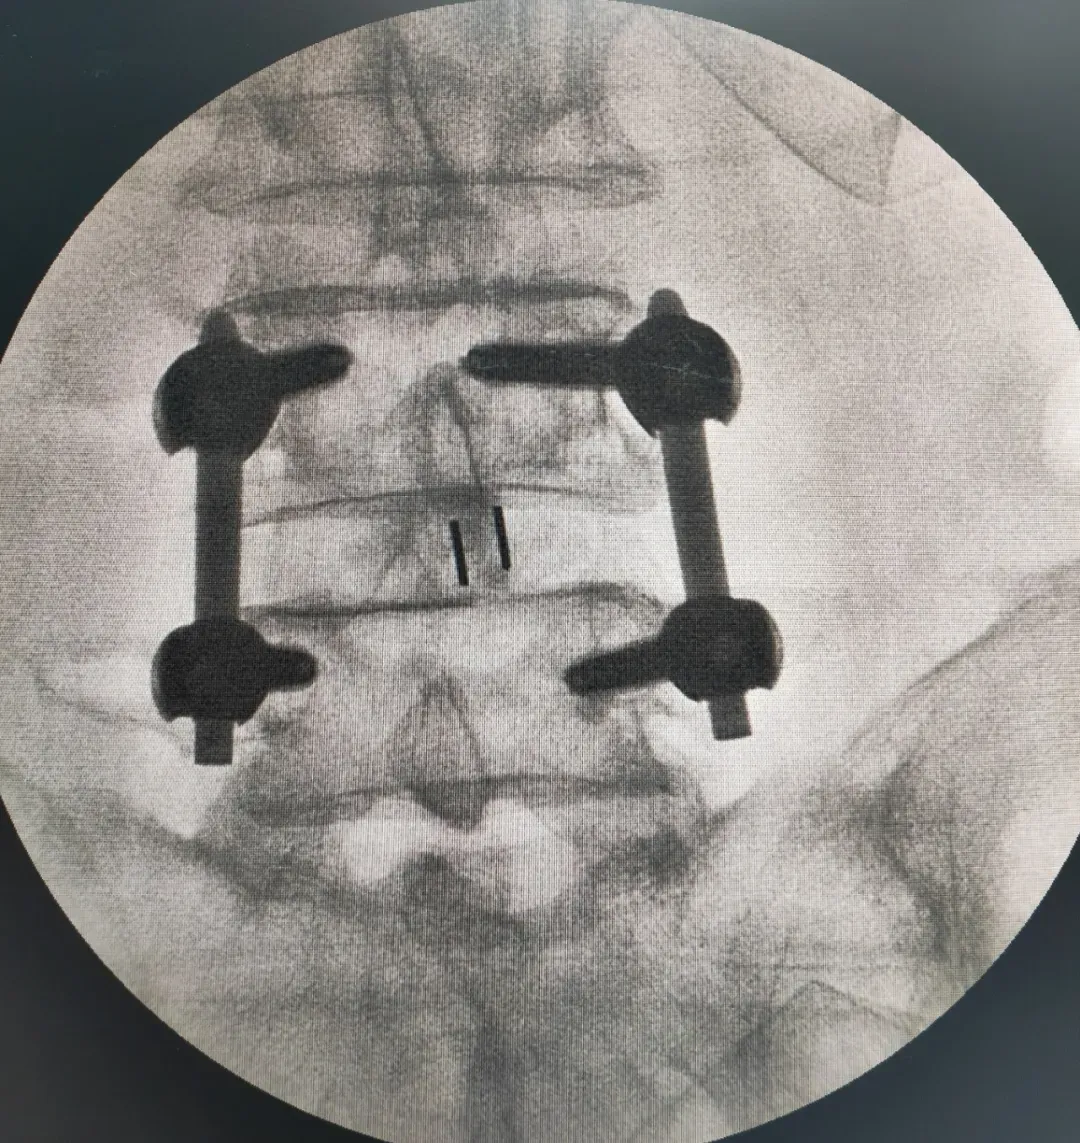

IMG_256 李龍主任詳細閱讀影像學資料并再次對患者進行全面評估,明確了病因:腰4-5節(jié)段重度椎管狹窄合并腰椎失穩(wěn)。這正是導致患者下肢劇烈疼痛和行走困難的“罪魁禍首”。李主任向患者及家屬詳細解釋了病情:椎管狹窄使得神經受壓,腰椎失穩(wěn)則加劇了這種壓迫和炎癥反應,保守治療在此階段難以解決根本問題。他建議施行微創(chuàng)減壓融合術,徹底解除神經壓迫,重建腰椎穩(wěn)定。 IMG_258 當聽到可以通過手術進行“減壓”時,被病痛折磨多年的老人仿佛看到了曙光,如同抓住了“救命稻草”。在充分理解手術必要性與微創(chuàng)技術的優(yōu)勢后,患者及家人消除了對高齡手術的恐懼,果斷接受了李龍主任提出的手術方案。經過周密的術前準備,手術如期進行。李龍主任團隊憑借精湛的微創(chuàng)技術,成功為患者實施了腰4-5微創(chuàng)減壓融合術。手術過程順利,術中出血極少。術后,困擾患者多年的腿疼癥狀得到了很大緩解。令人欣喜的是,在術后第三天,老人便在醫(yī)護人員指導下,佩戴支具下地行走。邁步的那一刻,患者及其家屬的臉上露出了久違的笑容。對梁振斌主任的精準初判、李龍主任的高超技術以及整個醫(yī)療團隊的精心照護表示了無盡的感激。 IMG_260 本例高齡患者的成功救治,充分體現(xiàn)了精準診斷、多學科協(xié)作以及現(xiàn)代脊柱微創(chuàng)技術的巨大優(yōu)勢。李龍主任提醒,如果腰腿痛長期保守治療無效,特別是疼痛加重、行走越來越困難的患者,應盡早到正規(guī)醫(yī)院就診,由醫(yī)生評估是否需要手術。微創(chuàng)手術技術成熟,可以為許多高齡、高風險患者提供安全有效的治療,避免延誤病情導致神經不可逆的損傷。(李 ? 勇)